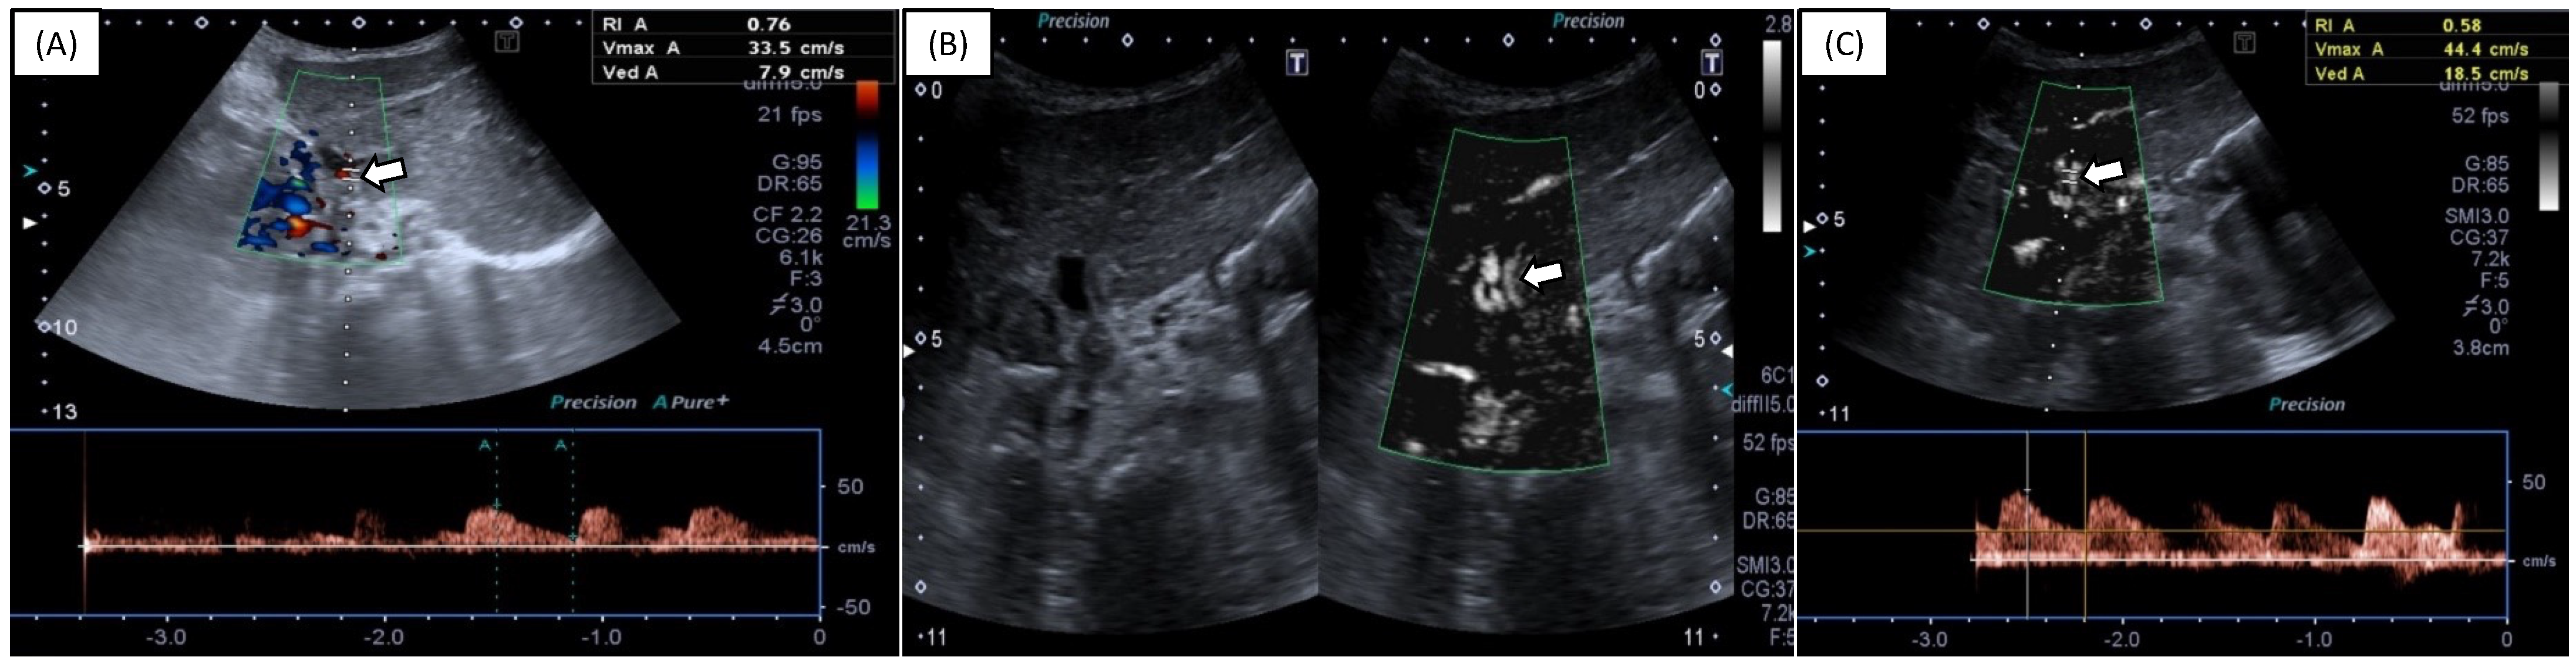

Superb Microvascular Imaging (SMI) Compared with Color Doppler Ultrasound for the Assessment of Hepatic Artery in Pediatric Liver Transplants: A Feasibility Study

- Gu, L.H.; Fang, H.; Liu, X.S.; Xia, Q.; Li, F.H. Additional value of superb microvascular imaging for assessing hepatic arterial blood flow after pediatric liver transplantation. Pediatr. Transplant. 2020, 24, e13785. [Google Scholar] [CrossRef]

- Jang, H.Y.; Kim, K.W.; Kim, S.Y.; Kim, J.S.; Choi, S.H.; Kim, S.Y.; Lee, S.G. Visibility of the graft hepatic artery using superb microvascular imaging in liver transplantation recipients: Initial experience. Acta Radiol. 2018, 59, 1326–1335. [Google Scholar] [CrossRef] [PubMed]